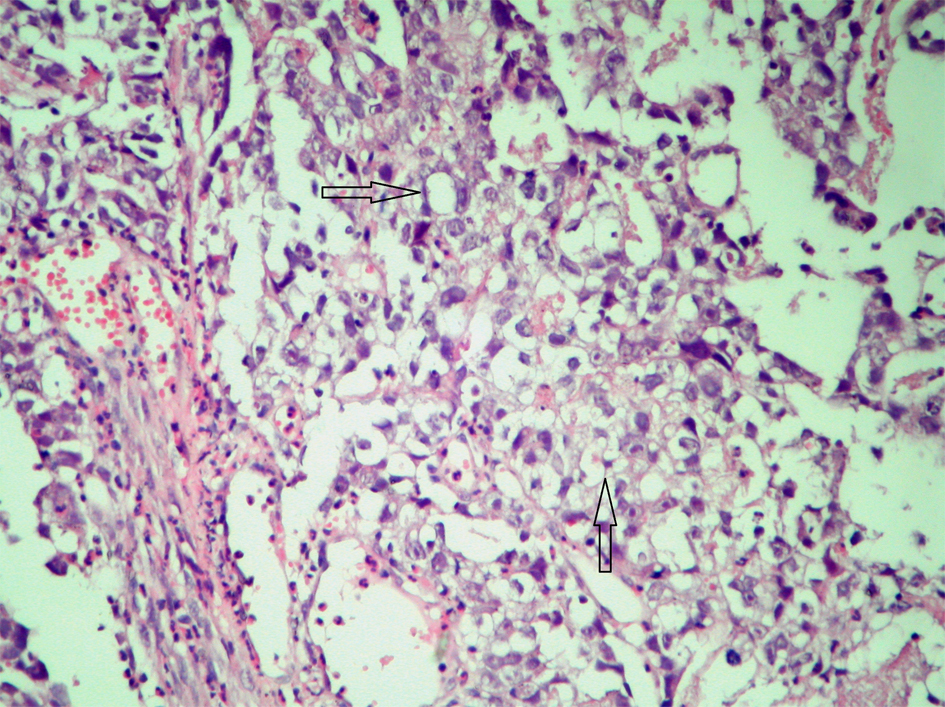

Microscopically the tumor cells were found as uniform with abundant clear cytoplasm, large necrosis areas and rosette structures and with sharply outlined cell membranes containing a large centrally located nucleus with hyper chromatic feature. In many areas, the tumor cells were arranged in nests outlined by fibrous bands and immunohistochemically these cells exhibited reactivity for α-fetoprotein (AFP) (Fig. 2, Immunoperoxidase, x 400). Based on the result of histopathological examination, germ cell tumor was diagnosed especially seminoma was considered. Tumor markers of the patient, were with in the normal limits (AFP: 1.77 ng/mL, human chorionic gonadotropin (HCG): 0.1 mIU/mL LDH: 178 U/L). Ultrasonography and computed tomography imaging of gonads (testes) did not show a primary tumor the patient was accepted as clinical stage-I. Adjuvant four cycles BEP (Bleomycin, Etoposit, Cisplatin) chemotherapy was given. After completion of four cycles chemotherapy, the patient followed up in remission for 8 months.

![]() Click for large image | Figure 2. AFP reactivity in tumor cells. |